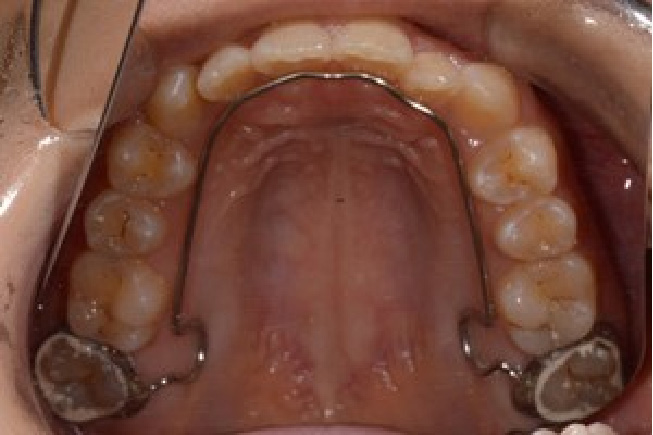

• 予防矯正

歯並びの改善や、筋機能改善(適応年齢3~17歳程度)

歯ならびだけでなく、口の周りや舌の筋肉の機能の改善。正常な成長発育を促す予防的な矯正治療。

【自費診療:プレオルソ:55,000円、交換:11,000円、 床矯正、その他装置 77,000円~】

• 器具イメージ1

• 器具イメージ2